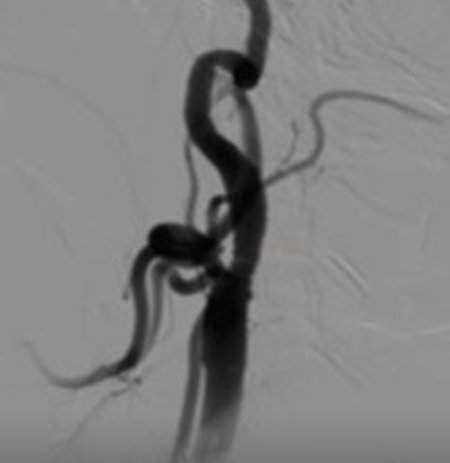

Outcomes observed in patients treated with image-guided, minimally invasive vascular procedures.

Results vary by patient and condition. Images are for educational purposes only.